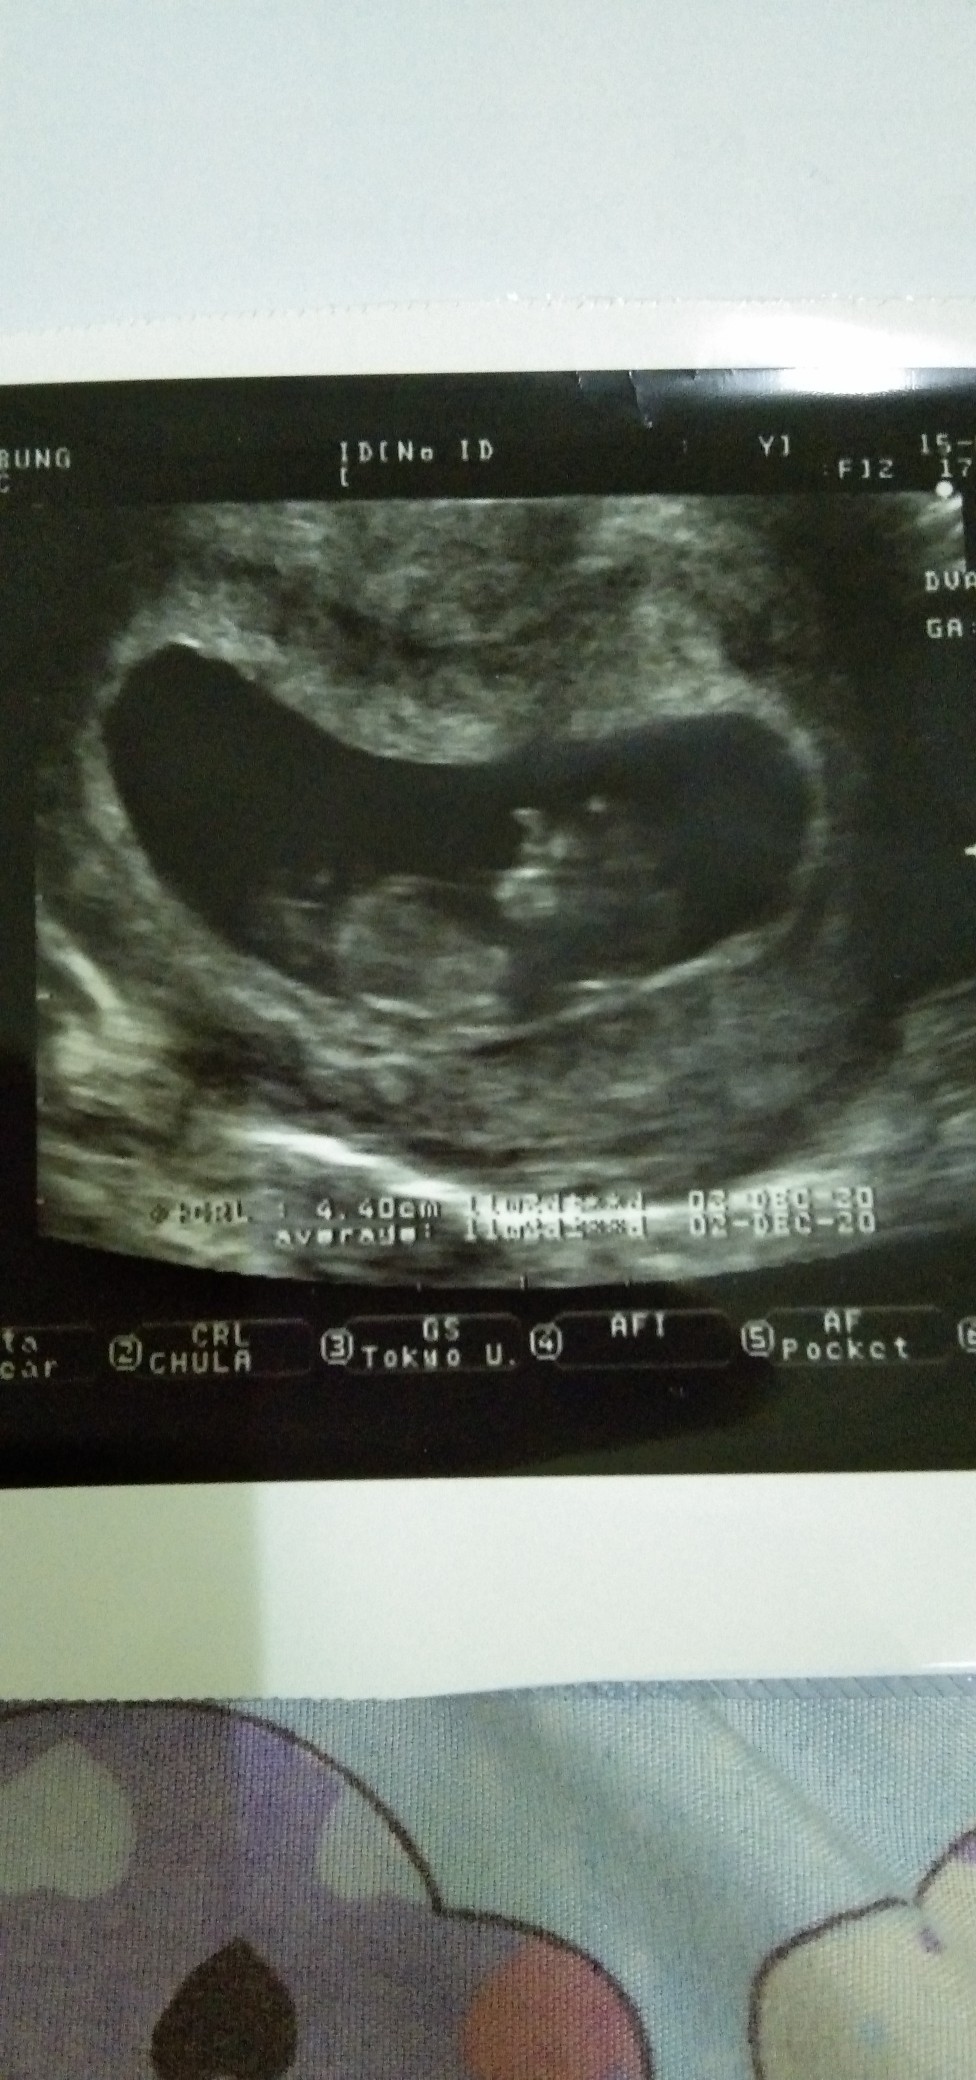

ขอดูใบซาวหน่อยจ้า เเล้วกำหนดคลอดวันที่เท่าไรกันค่ะ

12 ธันวาคมจ้า